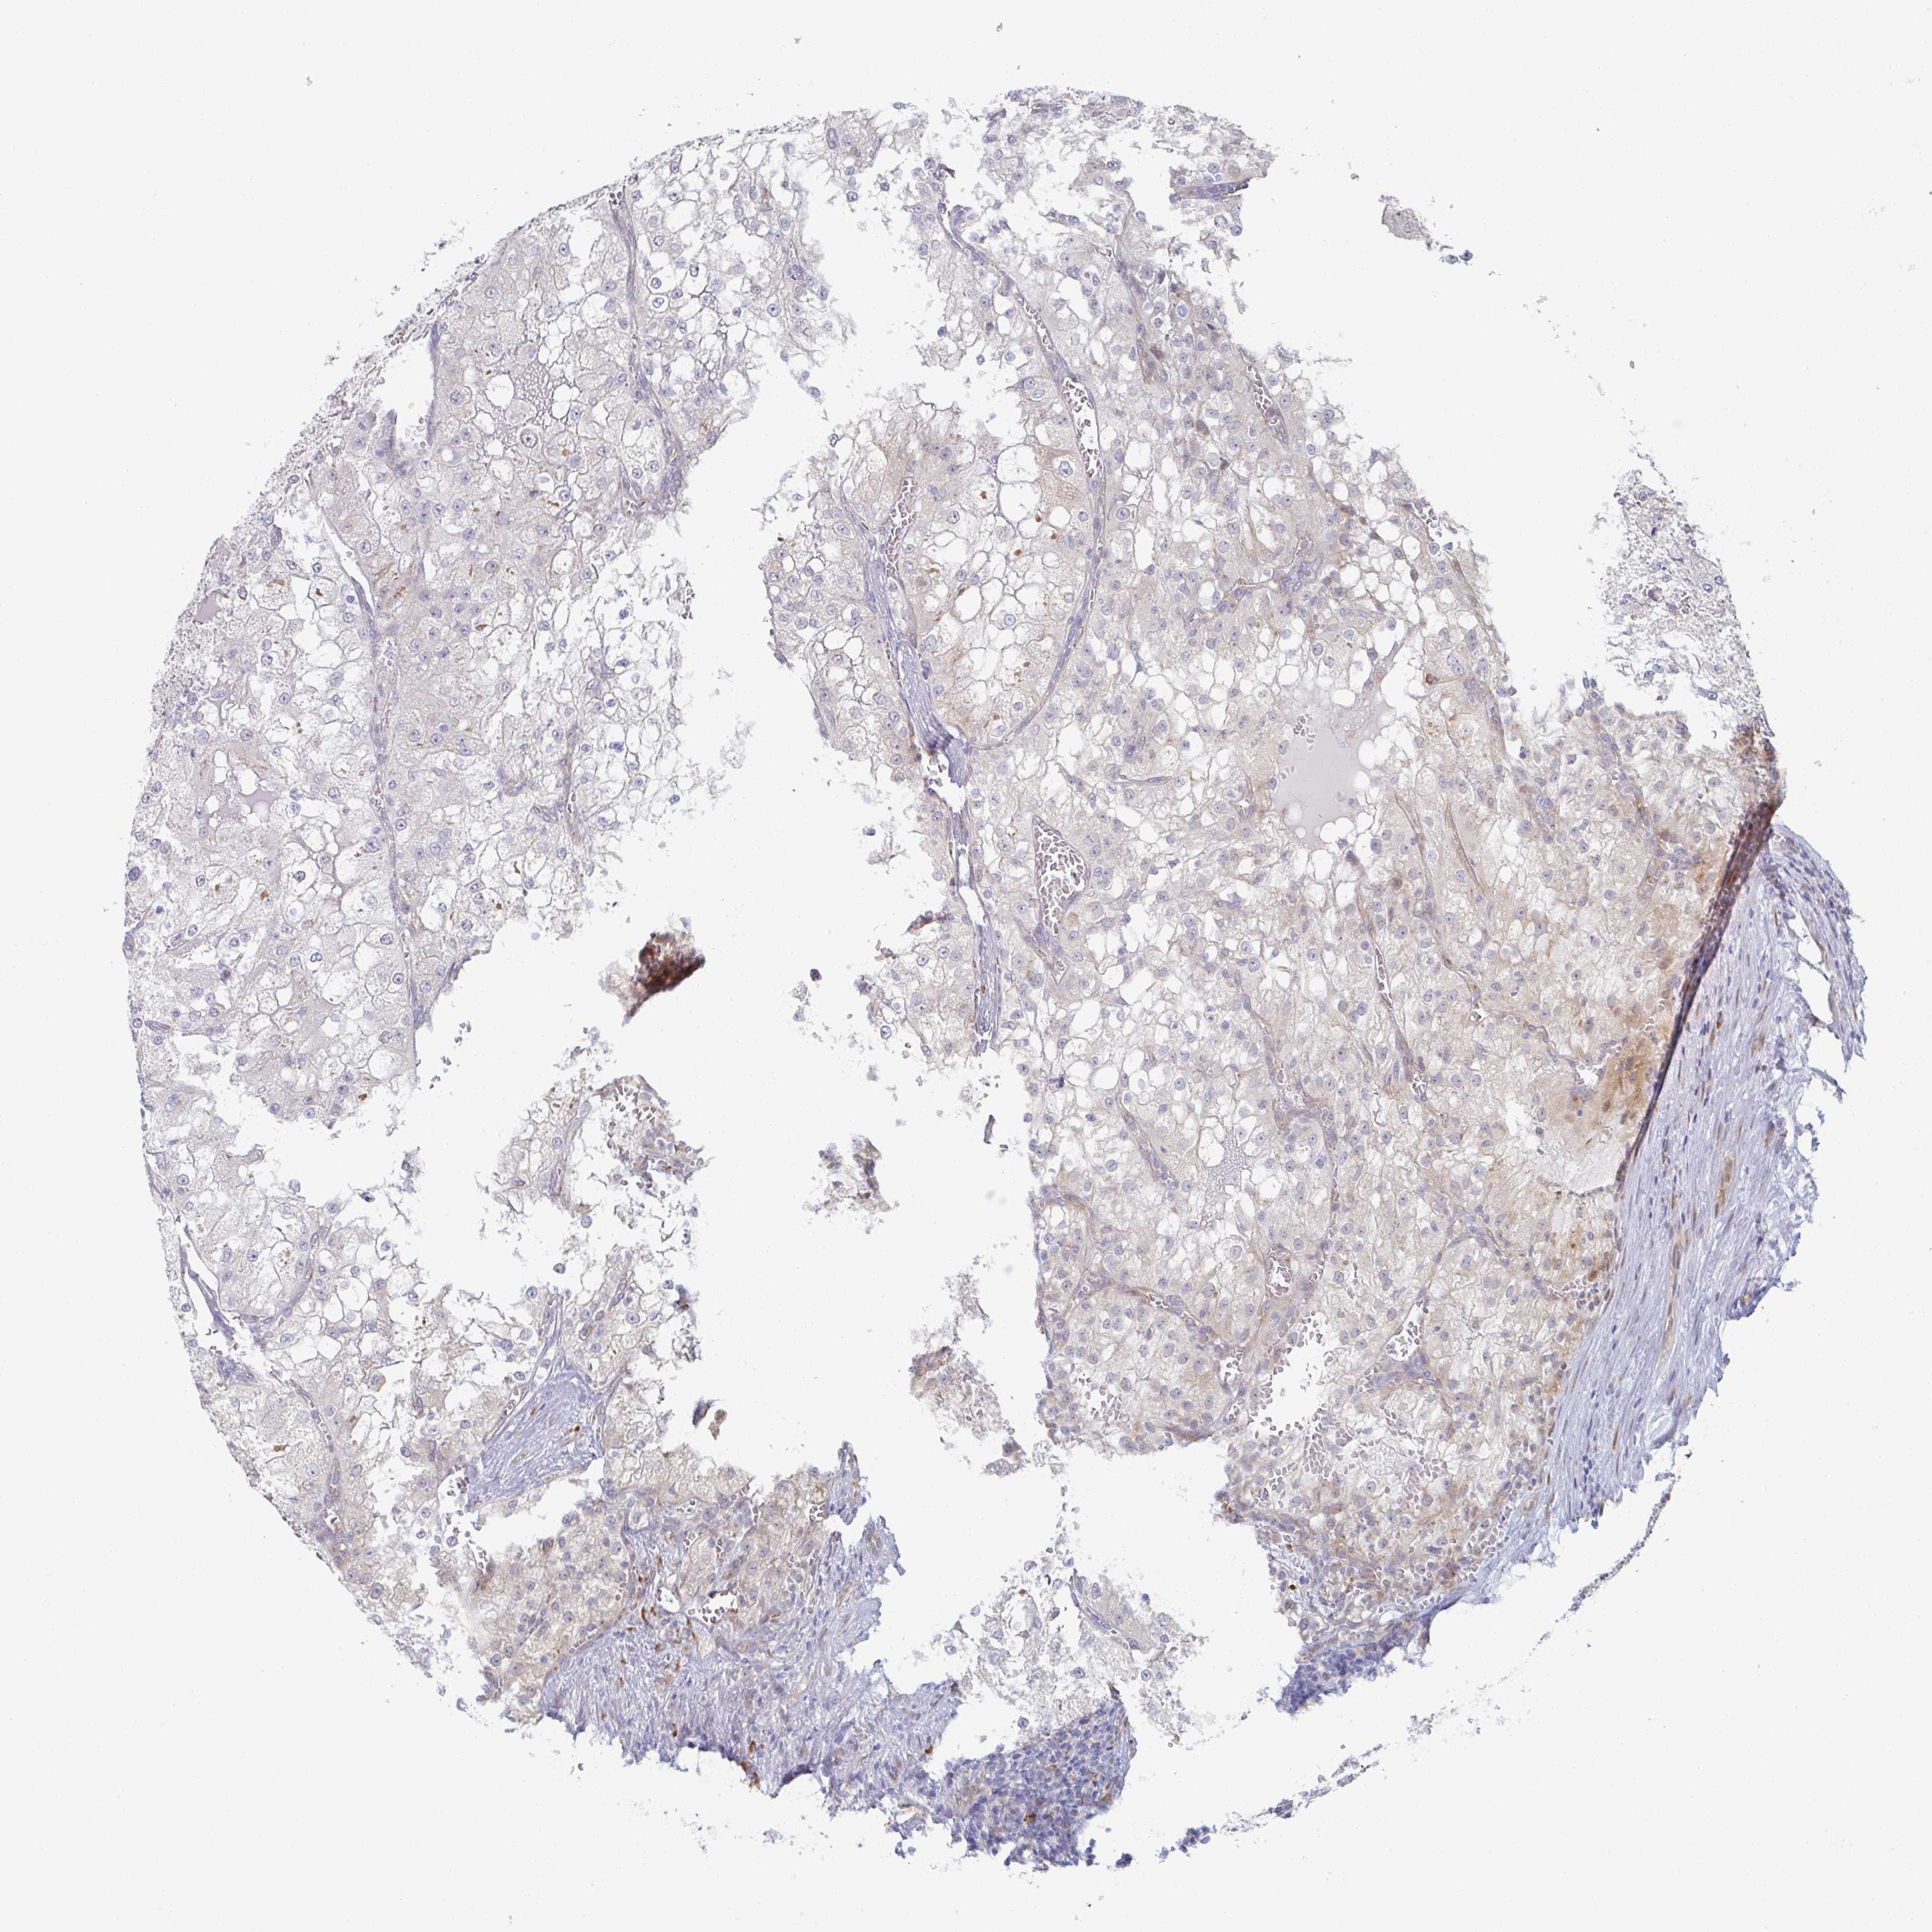

CANCER RENAL CANCER Show tissue menu

KICH TCGA KIRC TCGA KIRC VALIDATION KIRP TCGA PROTEIN RCC CPTAC PROTEIN EXPRESSION